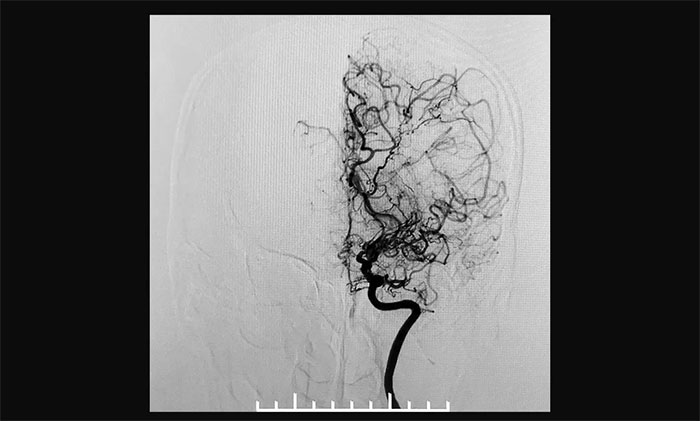

上海蓝十字脑科医院神经外科6A病区专家宫卫东主任介绍,烟雾病又称“自发性脑底动脉环闭塞症”,是一组以双侧颈内动脉末端和(或)大脑前动脉、大脑中动脉起始部缓慢进展性狭窄以致闭塞后,脑底出现代偿性异常血管网为特点的脑血管病,因其血管造影形似“烟雾”,故称为“烟雾病”。

▲异常血管网在脑血管造影时形似“烟雾”

据文献记载,烟雾病于20世纪60年代在日本被首先发现,其后世界其它国家相继发现相关病例。1969年,日本学者Suzuki及Takaku将该病称之为“moyamoya”。“ moyamoya”在日语中意为“喷出的烟雾”,“烟雾病”由此得名。